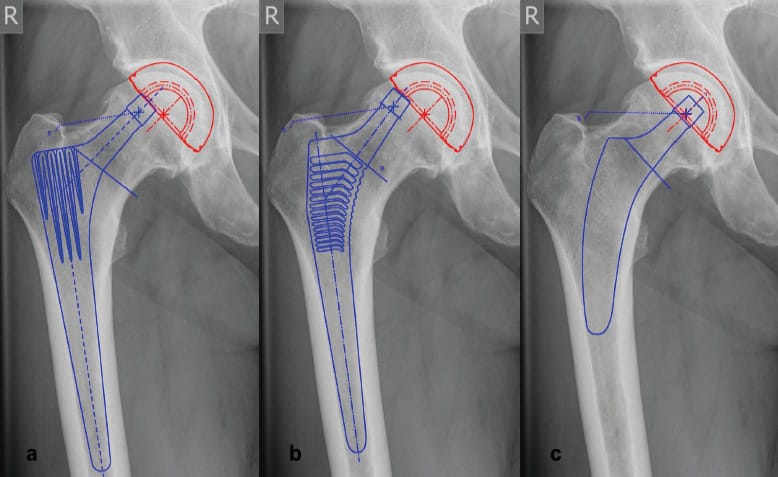

Conventional straight stems provide diaphyseal anchorage along with a mostly standardized level of osteotomy of the femoral neck. The preexisting hip anatomy can only be reconstructed by using different offset-versions of the implant. In extensive varus anatomies for example, this often cannot be achieved properly (Figure 4). Valgization has been found to be the limiting factor in the successful reconstruction of hip geometry also in many previous short-stem designs, causing reduced offset and increased leg length [10] Höhle P, Schröder SM, Pfeil J (2015) Comparison between preoperative digital planning and postoperative outcomes in 197 hip endoprosthesis cases using short stem prostheses. Clin Biomech 30:46–52. doi: 10.1016/j.clinbiomech.2014.11.005..

Reconstruction of the femoral offset is highly dependent on the ability to reproduce different CCD-angles [18] Kutzner KP, Pfeil J, Kovacevic MP (2017) Preoperative digital planning versus postoperative outcomes in total hip arthroplasty using a calcar-guided short stem: frequent valgization can be avoided. Eur J Orthop Surg Traumatol 27:643–651. doi: 10.1007/s00590-017-1948-2.. The

reconstruction of different CCD-angles, in this regard, seems to be the key to accomplish the retainment of the hip anatomy.

In calcar-guided short-stem THA, stem alignment can be individualized, which supports the successful reconstruction of the femoral offset [16] Kutzner KP, Freitag T, Donner S, et al. (2017) Outcome of extensive varus and valgus stem alignment in short-stem THA: clinical and radiological analysis using EBRA-FCA. Arch Orthop Trauma Surg 137:431–439. doi: 10.1007/s00402-017-2640-z.. Guiding the stem alongside the calcar, the positioning of the stem in the proximal femur is dependent on the resection level of the femoral neck. Given a preexisting varus anatomy, a high resection also results in a varus position of the implant, maintaining a large femoral offset. On the other hand, given a preexisting valgus anatomy, a low resection results in a valgus position, causing a small femoral offset [14] Kutzner KP, Pfeil J (2018) Individualized Stem-positioning in Calcar-guided Short-stem Total Hip Arthroplasty. J Vis Exp. doi: 10.3791/56905 (Figure 5) Consequently, this allows a broad reconstruction of CCD-angles and thus enables a precise preservation of hip geometry.